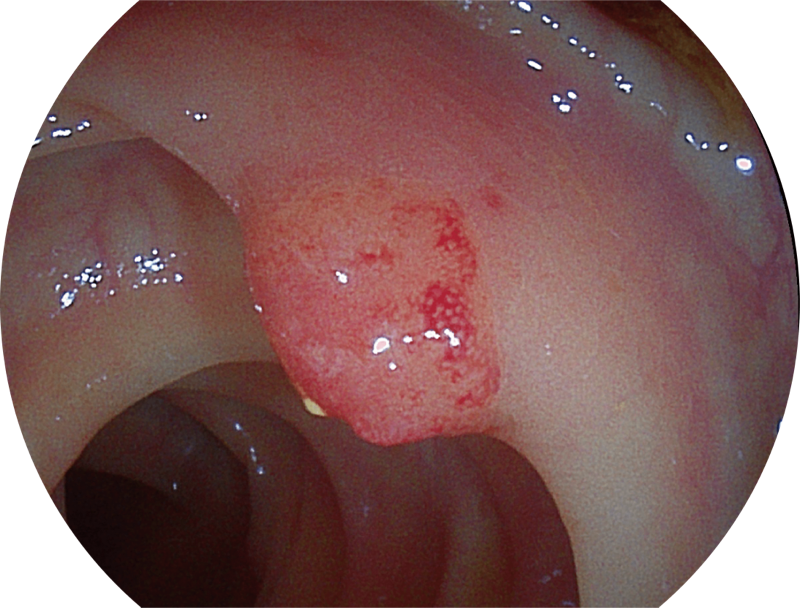

百万级像素高清传感器,1080P全高清视频信号输出,图像清晰。

能够凸显黏膜浅层和中层血管轮廓,适用于中、远景观察下的病灶识别和早癌筛查。

SFI图像

能够凸显黏膜浅层血管轮廓和黏膜表面微结构,适用于中、近景观察下的早癌精确诊断。